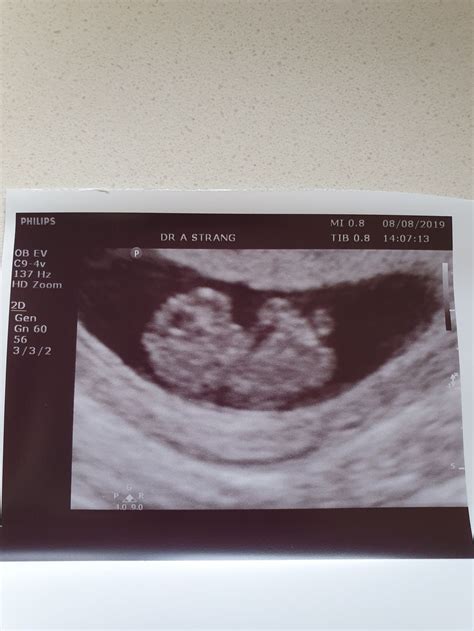

At 9 weeks, the fetus is still very small, but several key features can be visualized:

• Embryo: The embryo itself, which is about the size of a grape, can be seen with a distinct head and body.

• Fetal Heartbeat: The heartbeat is usually visible and audible, providing reassurance of the fetus’s health.

• Crown-Rump Length (CRL): This is the measurement from the top of the head to the bottom of the buttocks. At 9 weeks, the CRL is typically around 21-27 mm.

• Gestational Age: The ultrasound can help confirm the gestational age, which is crucial for monitoring the pregnancy and planning future care.